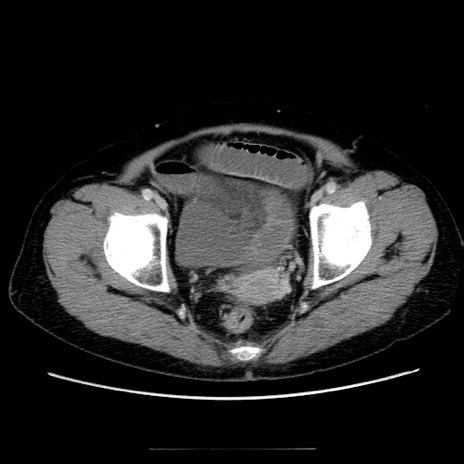

症例5(横断像)

【症例】70歳代女性

【主訴】お腹が張る

【現病歴】1週間くらい前から腹部膨満の自覚あり。昨日夜から増悪したため、本日救急外来受診。

【身体所見】意識清明、BT 36.5℃、BP 165/106mmHg、HR 80bpm、SpO2 98%、腹部:膨満、軟、自発痛・圧痛なし、触診にて不快感あり、腸蠕動音:減弱

【データ】WBC 12600、CRP 1.04